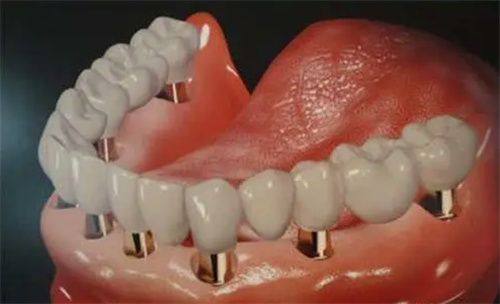

活动义齿一般多少钱一颗费用?2026年最新价格揭秘! 文章揭秘2026年活动义齿最新价格。通常镶活动假牙一颗1000 - 3000元,不同类型费用有别。如隐形义齿1000 - 1200元,便宜但寿命短、咀嚼差;钴铬合金等1500 - 2000元,强度好、使用久;纯钛基托2000 - 3000元,舒适美观。此外,地区、医院等级和医生水平也影响价格,选义齿要综合考量。 活动义齿 2026年03月04日 0 点赞 0 评论 7 浏览

活动义齿哪种最舒服还不伤害基牙?揭秘3种最佳选择! 本文围绕“活动义齿哪种最舒服还不伤害基牙”展开。首先强调了活动义齿舒适与护基牙的重要性,接着介绍了纯钛金属基托活动义齿等三种义齿的特点,包括舒适度、对基牙的影响、价格等。还给出选择建议,要考虑口腔状况、经济因素,并听取医生建议。最后提醒佩戴后注意适应期、清洁和饮食,综合考量选适合自己的义齿。 活动义齿 2026年03月04日 0 点赞 0 评论 12 浏览

补一颗活动义齿多少钱?揭秘真实费用与选择技巧! 本文围绕补一颗活动义齿的费用及选择技巧展开。费用大致在100 - 300元,受材料、修复难易、医院级别、当地经济等因素影响。不同材料义齿各有特点和价格区间。选择时要综合自身情况,选正规机构,多对比。此外,后期维护有成本,需正确佩戴清洁。提醒大家综合考量价格、质量和舒适度,必要时咨询医生。 活动义齿 2026年03月04日 0 点赞 0 评论 7 浏览